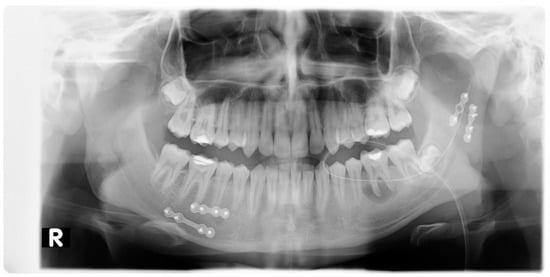

2. Materials and Methods